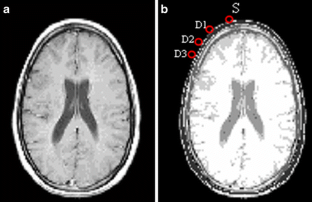

Theoretical analysis of spatial distribution of near-infrared light propagation in head tissues is very important in brain function measurement, since it is impossible to measure the effective optical path length of the detected signal or the effect of optical fibre arrangement on the regions of measurement or its sensitivity. In this study a realistic head model generated from structure data from magnetic resonance imaging (MRI) was introduced into a three-dimensional Monte Carlo code and the sensitivity of functional near-infrared measurement was analysed. The effects of the distance between source and detector, and of the optical properties of the probed tissues, on the sensitivity of the optical measurement to deep layers of the adult head were investigated. The spatial sensitivity profiles of photons in the head, the so-called banana shape, and the partial mean optical path lengths in the skin-scalp and brain tissues were calculated, so that the contribution of different parts of the head to near-infrared spectroscopy signals could be examined. It was shown that the signal detected in brain function measurements was greatly affected by the heterogeneity of the head tissue and its scattering properties, particularly for the shorter interfibre distances.

Mansouri, C., L’Huillier, JP., Kashou, N.H. et al. Depth sensitivity analysis of functional near-infrared spectroscopy measurement using three-dimensional Monte Carlo modelling-based magnetic resonance imaging. Lasers Med Sci 25, 431–438 (2010). https://doi.org/10.1007/s10103-010-0754-4